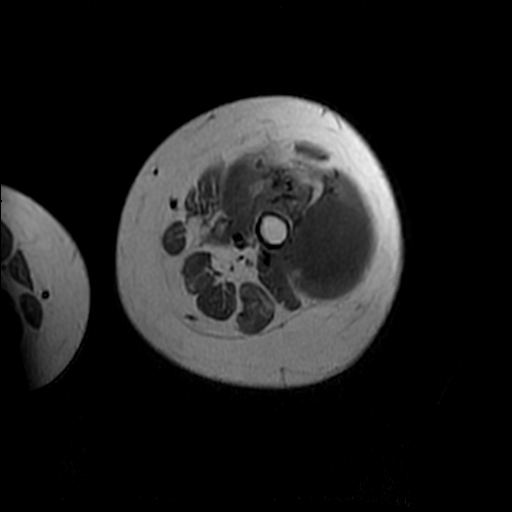

左侧大腿外伤10余年,当时情况不清,发现左侧大腿肿胀7年余,而后又有多次外伤史,近1年来出现疼痛,减重半年。查体:左侧大腿肿胀明显,皮温、肤色正常。

软组织肿块,股骨破坏,增强不均匀强化-----支持恶性肿瘤